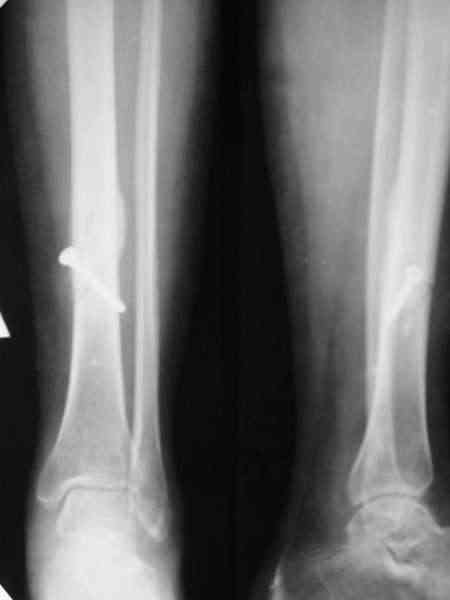

Мы лет 5-6 назад, когда еще не делали закрытое штифтование, сделали с десяток подобных операций, в том числе несколько на бедре. Репозиция закрытая, кортикальный винт 4,5 мм через прокол. Ближний кортекс рассверливали до 5 мм после нарезания резьбы, то есть получался нормальный компрессирующий винт. Аппараты только уже делали монолатеральные стержневые, чтобы не прошивать насквозь мышцы спицами (пример в приложении).

Хотя, конечно, вполне можно и обычные кольца со

спицами.

Типичный косо-спиральный перелом голени с низкой энергией, большеберцовая внизу, а сверху малоберцовая, и применение интрафрагментарного компрессионного шурупа можно оправдать, когда для

Если винт все-таки стягивающий (компрессирующий), а не "позиционный", то это чистой воды философия АО, так называемый принцип Mini-Max. Философии Илизарова , пожалуй пртиворечит: фиксация не совсем внеочаговая:)